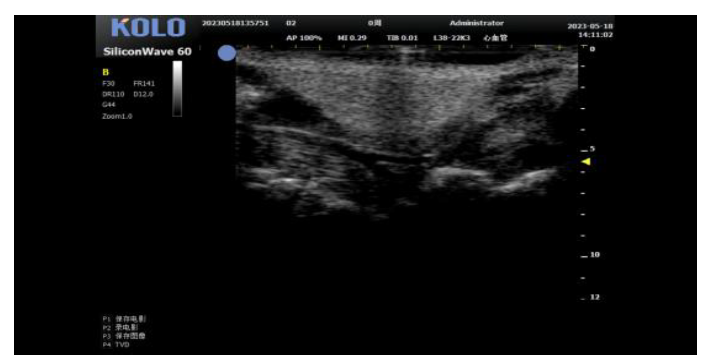

基于CMUT 半导体超声技术,集成多项发明专利,珂纳医疗精心研发出 SiliconWave 60 超高频小动物超声成像系统。该系统微米级的超高清分辨率,8-62 MHz 超宽频段和丰富灵敏的彩色多普勒功能为临床前科研用户观察小动物的心血管、腹部脏 器、浅表组织及胚胎等提供了清晰多彩的超声图像。系统的实时无创操作也为科研实验 的反复验证,长期动态观察等提供了极大的便利性。

1. 小鼠心脏研究---左心室(长+短轴+M 超)

2. 小鼠心脏研究---四腔心(长轴+血流测速)

4、内脏测量

5肿瘤测量(肿瘤大小精确测量)